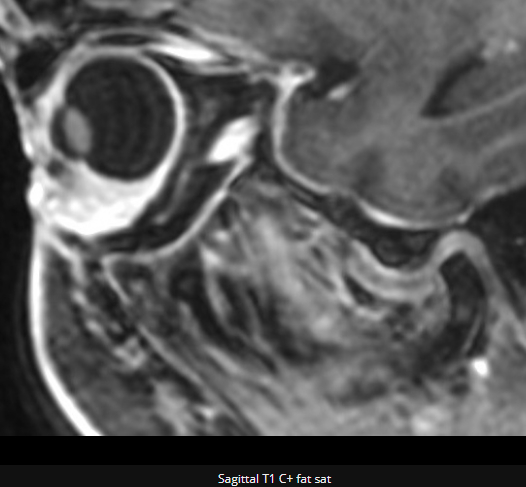

右上眼睑皮下见一结节状异常信号,图A-D 轴位平扫示T2WI 呈高低混杂信号,T1WI呈低信号,T2脂肪抑制呈混杂高信号,DWI为低信号,病灶内见诸诸序列为低信号的散在结节,图E、图F增强轴位及矢状位示病变呈明显不均匀强化,T2WI 显示高信号部分未见强化,右眼眶内组织未见明显异常。